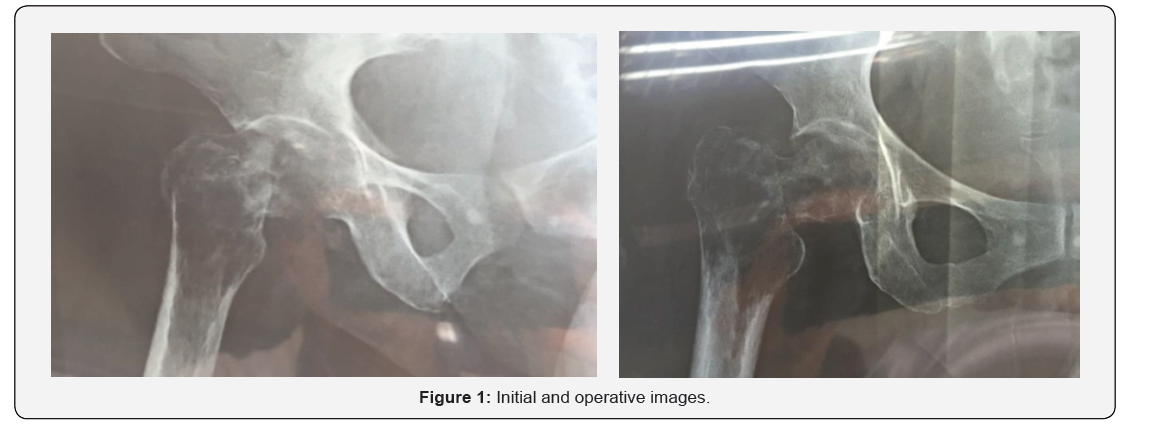

General notes on metastatic breast cancer. Breast cancer is the most frequent type in women (skin cancer is excluded), it is the second most frequent cause of cancer death in women. Metastatic breast cancer will generate most of such deaths. About 5% of women have metastatic breast cancer when they are first diagnosed. More research is needed to determine how many people with non-metastatic breast cancer subsequently have metastatic breast cancer. The 5-year survival rate indicates the percentage of people who survive at least 5 years after the cancer is detected [1]. The 5-year survival rate of women with metastatic breast cancer is 27%. The 5-year survival rate of men with metastatic breast cancer is 20%. Breast cancer may be limited to the breast and / or nearby lymph node regions, which we call early stage or locally advanced cancer (Figures 1 & 2).

In the anteroposterior Rx of the right hip at a real distance, we observed an extracapsular pathological fracture, with a main intertrochanteric line, with a wide osteolytic image that extends from the femoral neck to the whole trochanter mass, and extends 2.5 cm sub trochanteric , with 6 cm of proximal femur with tumor image. The complements showed haemoglobin at 7.3 g/L, phosphatase at 286 U/L, other tests within normal ranges, negative chest and abdomen T.A.C, bone scintigraphy, and hip CT showed evidence of metastatic fracture. Three units of red blood cell concentrate compatible with group and Rh factor and subsequent control are transfused, with a result of haemoglobin at 12 g/l; We prepare the patient for a surgical first time by tumor biopsy.